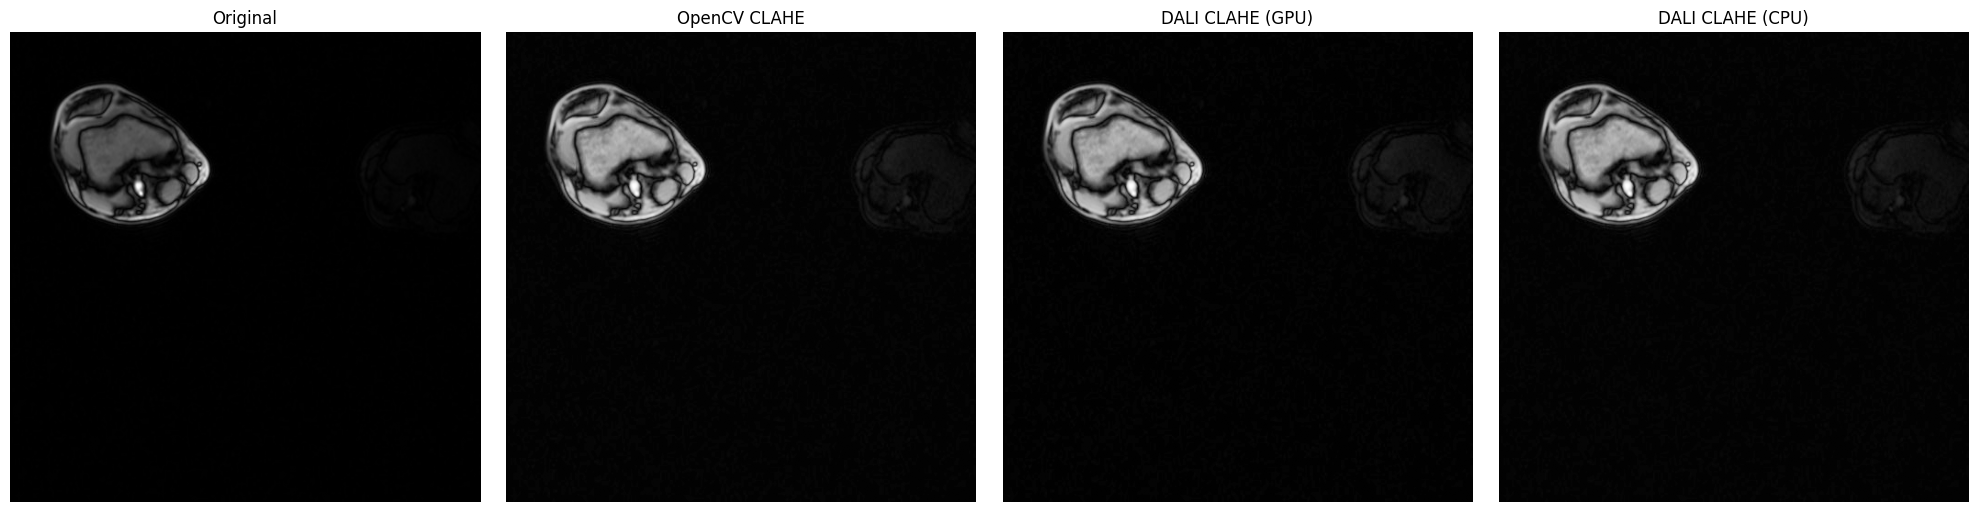

DALI CLAHE vs OpenCV CLAHE on Medical Imaging (Knee MRI)#

This section demonstrates CLAHE on real low-contrast medical imaging data - knee MRI slices from the DALI_extra repository. Medical imaging is where CLAHE truly shines, as these images often have naturally low contrast that benefits significantly from adaptive histogram equalization.

The knee MRI slices (db/3D/MRI/Knee/npy_2d_slices/STU00001/SER00001/) are perfect for demonstrating CLAHE because:

• Low local contrast: MRI data typically has subtle tissue boundaries

• Grayscale: Single-channel data ideal for CLAHE

• Real-world clinical data: Demonstrates practical medical imaging applications

• Multiple sequences: 15 different series (SER00001-SER00015) available for experimentation

fig, axes = plt.subplots(1, 4, figsize=(20, 5))

axes[0].imshow(mri_array.squeeze(), cmap="gray")

axes[0].set_title("Original")

axes[0].axis("off")

axes[1].imshow(opencv_result.squeeze(), cmap="gray")

axes[1].set_title("OpenCV CLAHE")

axes[1].axis("off")

axes[2].imshow(dali_gpu_flat, cmap="gray")

axes[2].set_title("DALI CLAHE (GPU)")

axes[2].axis("off")

axes[3].imshow(dali_cpu_flat, cmap="gray")

axes[3].set_title("DALI CLAHE (CPU)")

axes[3].axis("off")

print("\nImplementation Comparison Metrics:")

print("=" * 60)

print(f"OpenCV vs DALI GPU:  MSE = {mse_ocv_gpu:.4f}, MAE = {mae_ocv_gpu:.4f}")

print(f"OpenCV vs DALI CPU:  MSE = {mse_ocv_cpu:.4f}, MAE = {mae_ocv_cpu:.4f}")

print(f"DALI GPU vs CPU:     MSE = {mse_gpu_cpu:.4f}, MAE = {mae_gpu_cpu:.4f}")

print("\nNote: Lower values indicate closer agreement between implementations.")